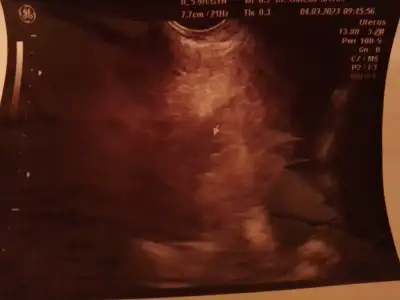

Kızlar merhaba hatırlarsanız sizin sayenizde gecen hafta hamile olduğumu öğrendim beta 191 çıkmıştı 1 Mart'ta tekrar kan verdim 293 çıktı ve dün gene verdim 1919 çıktı dun de alttan muayneyle minnacık keseyi gördüm doktorum ilkten 4 buçuk haftalık falan dedi sonra tekrar sorduğumda 20 günlük dedi 20 günlük bebek kesesi gözükür mu kafam allak bullak Allah rızası için yardım oldu edin😔

Buda kesemiz ☺️

Eklentiler

• 16780392465454327895766360070099.webp

16780392465454327895766360070099.webp

17,6 KB · Görüntüleme: 138